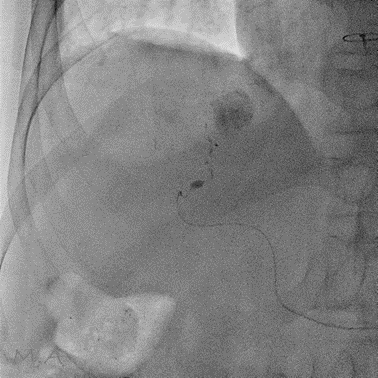

X線透視

当院ではFUJI製とCanon製のX線透視装置を導入しています

透視装置はX線を断続的に照射しながら画像にすることで、消化管の動きや造影剤の流れ、カテーテルの位置などをその場で確認することができます。

主な検査や治療の内容として、胃透視(胃がん健診)、透析患者さんへのシャントPTA(経皮的血管形成術)、カテーテルやチューブの挿入・確認、ERCP(内視鏡的逆行性胆道膵管造影)等の内視鏡を併用した治療などを行っています